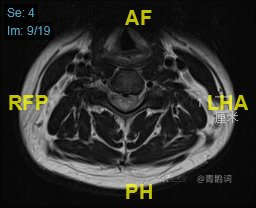

颈部磁共振平扫:

颈部磁共振平扫后增强: